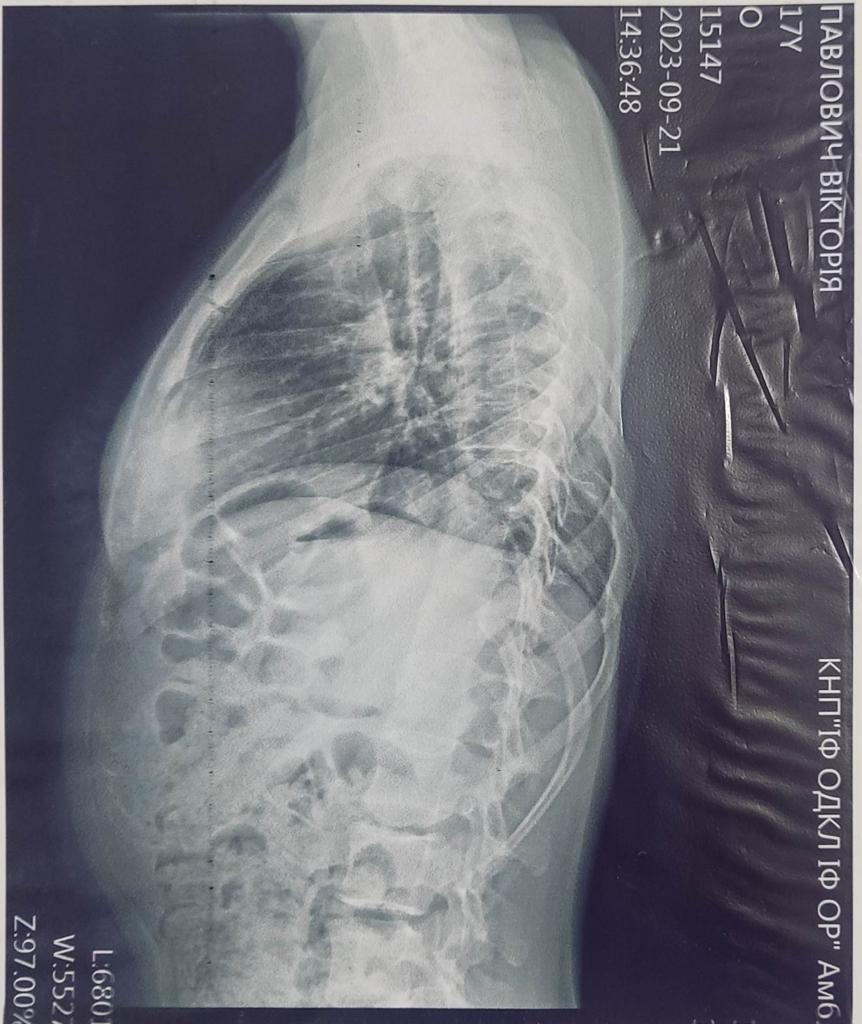

Victoria Pavlovich born on January 3, 2006.

Our family: Pavlovich Viktoriya Romanivna – daughter.